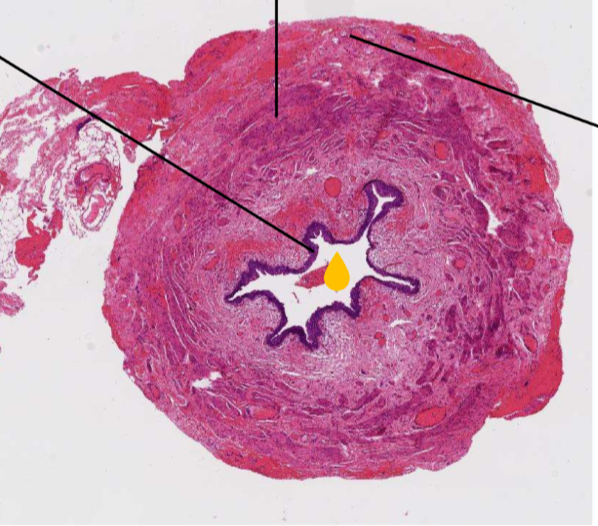

12

Q

A

de l’Ext vers l’intérieur dans cette lame de l’uretère en HE

• adventice(rose)

• musculeuse (mauve)

• muqueuse (violet=urothélium)